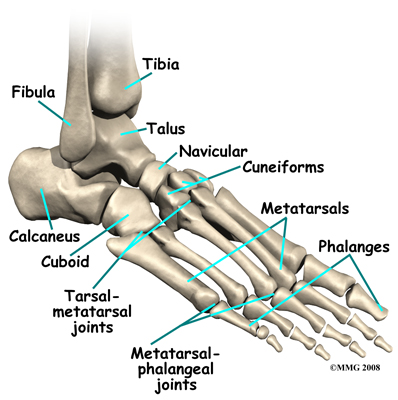

The skeleton of the foot centers around the talus, or ankle bone, that forms the main part of the ankle joint. The two bones of the lower leg, the large tibia and the smaller fibula, come together at the ankle joint around the talus to form a very stable structure.

The foot is able to bend up and down due to the joint formed by the tibia, fibula, and talus.

The foot is able to bend up and down due to the joint formed by the tibia, fibula, and talus.

The two bones that make up the back part of the foot (sometimes referred to as the hindfoot) are the talus and the calcaneus. The calcaneus is the heel bone. The talus is connected to the calcaneus at the subtalar joint. The subtalar joint allows the foot to rock from side to side. People with flatfeet usually have more motion at the subtalar joint than people who do not have flatfeet. This increased flexibility of the subtalar joint results in many compensatory actions of the foot and ankle in order to maintain proper foot alignment during standing and walking.

Just down the foot from the ankle is a set of five bones called tarsal bones that work together as a group and are termed the midfoot. These tarsal bones are unique in the way they fit together. There are multiple joints between the tarsal bones. When the muscles of the foot and leg twist the foot inwards, these bones lock together and form a very rigid structure. When they are twisted in the opposite direction, they become unlocked and allow the foot to conform to whatever surface the foot is contacting.

The tarsal bones are connected to the five long bones of the foot called the metatarsals. The two groups of bones are fairly rigidly connected, without much movement at the joints that connect them. Finally, there are the bones of the toes, called the phalanges. The metatarsals and phalanges make up the forefoot.